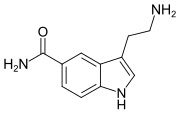

| 5-CT | artificial | 5-CONH2 | H | H | 5-Carboxamidotryptamine | 74885-09-9 |